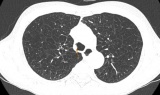

Tin mới y tế ngày 14/12: Khám sức khỏe tầm soát ung thư, phát hiện hai khối u gan -